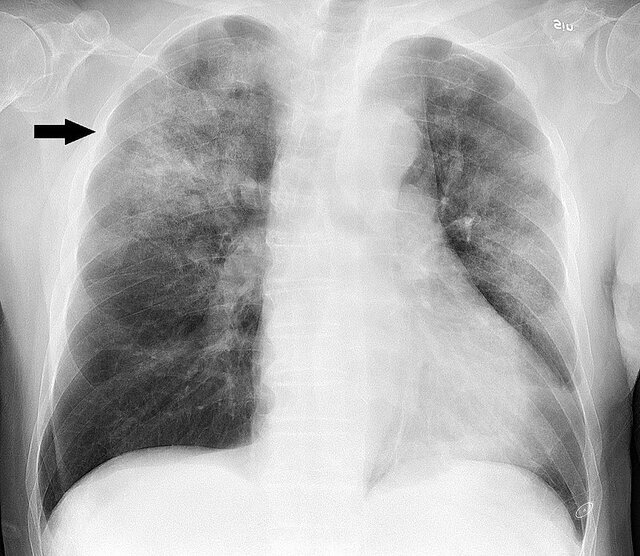

ذات‌الریه، یک عفونت حاد تنفسی است که ریه ها را تحت تاثیر قرار می دهد. این بیماری سالانه جان حدود ۲.۵ میلیون بزرگسال و کودک را در سراسر جهان می گیرد.

ذات الریه می تواند ریه های افراد را به شدت تحت تاثیر قرار دهد و معمولاً ناشی از عفونت ویروسی یا باکتریایی است که باعث پاسخ التهابی در ریه ها می شود. همچنین کووید۱۹ نیز می تواند منجر به ذات الریه شود که به ریه ها آسیب جدی وارد کند.